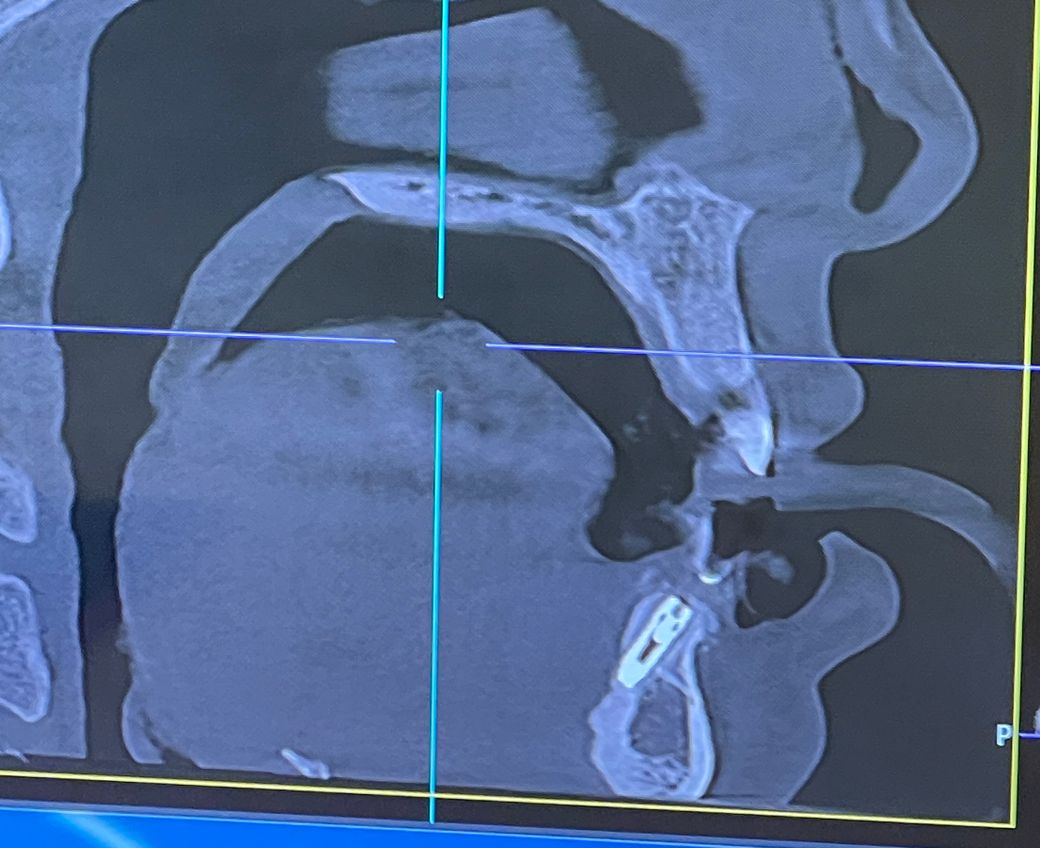

턱뼈 속이 아닌 뒤에 식립되었는데 아랫니 각도상

턱뼈 속으로 넣게 되면 뒤로 치아가 나오게 되어

어쩔 수 없다고 합니다.

그리고 앞쪽 뼈가 너무 얇아 앞쪽은 골 이식을하고

뒤로 최대한 붙인거라고해요.

설측 뼈에 임플란트가 가깝워 보이긴 하지만, 큰 문제가 잇어 보이진 않습니다. 너무 걱정하지 않으셔도 됩니다.

임플란트가 식립된 각도는 크게 문제가 없는 것으로 보입니다. 각도가 앞으로 기울어져 있다고 해도 보철물을 만들 때는 그의 상당하는 기둥을 커스텀에서 만들 수 있기 때문입니다. 너무 걱정하지 않으셔도 될 것으로 생각됩니다

사진상으로는 잇몸뼈 설측(혀 쪽) 피질골이 완전히 천공되거나 하지는 않았기 때문에 큰 문제는 없을 것으로 예상됩니다.

보철물 계획에 따라 좀 다를 수 있으나 크라운 보철물을 올렸을때 각도가 식립 각도와 다르면 하중이 엉뚱한 곳으로 가해지며 금방 부러질 수도 있습니다. 이건 치과의사가 크라운 보철물을 어떻게 올리고, 위아래 앞니 교합을 어떻게 할 것인지에 따라 조금 다를 것 같습니다.